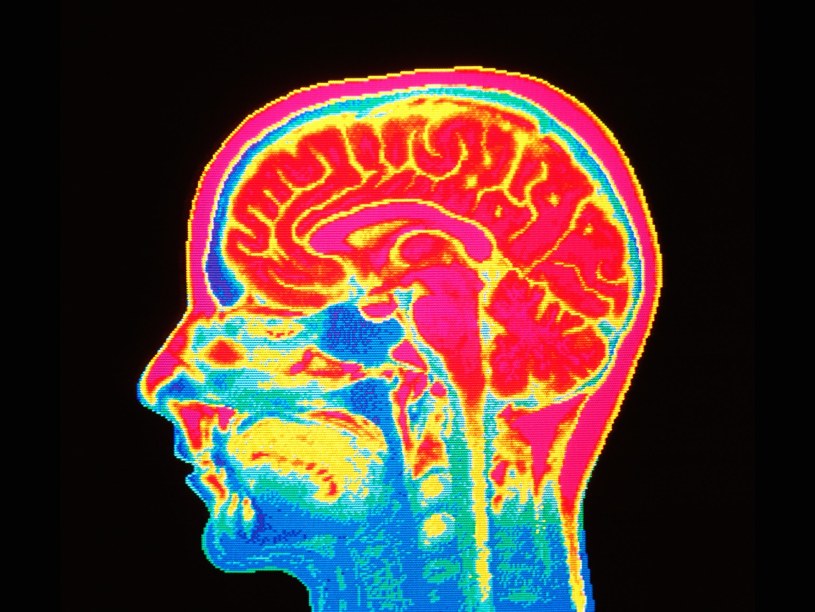

In this incident I also received a severe brain injury called a TBI. This left me with constant non-stop headaches and severe migraines that have me in and out of the emergency room regularly (twice this month alone).

I have had all kinds of CT scans and MRI’s. In fact I just had one MRI last week and will be getting two more MRI’s on the 29th. I also will be getting another CT scan which will be my 2nd this year. Not to mention several X-Rays of various parts of my body to. And in February I am getting an ocular scan to check my optic nerve and some other things that might be causing issues.

I have also since developed some pretty bad tremors that mostly affect my right side. The Veteran Affairs Hospital is currently trying to diagnose these tremors and have arranged for me to get a DaTscan. I have never heard of this type of scan before and thought I needed to research it. Hence this article.